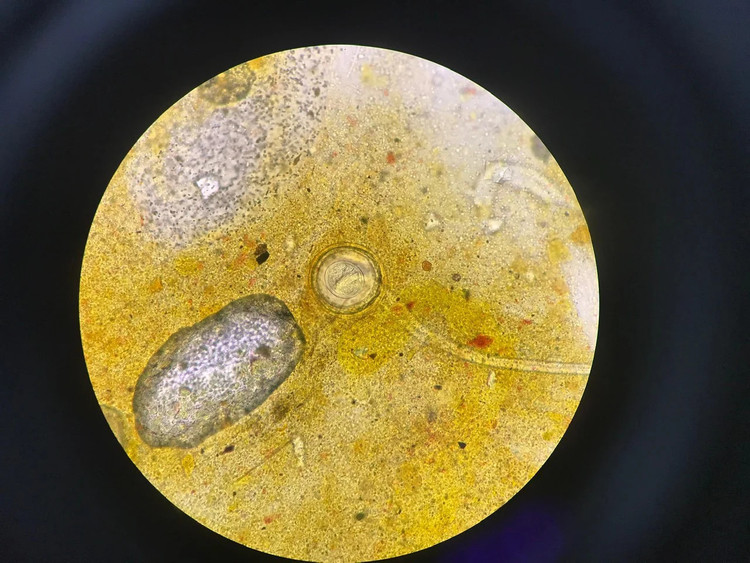

Bệnh nhi được gia đình đưa đến Bệnh viện Đặng Văn Ngữ khám sức khỏe. Kết quả xét nghiệm phát hiện có trứng sán dây nhỏ Hemynolepis spp đặc hiệu trong mẫu phân. Bệnh nhi được chẩn đoán mắc bệnh sán dây nhỏ Hymenolepiasis (hay còn gọi sán dây chuột).

| Trứng sán dây chuột trong mẫu phẩm của bệnh nhân khi soi qua kính hiển vi |